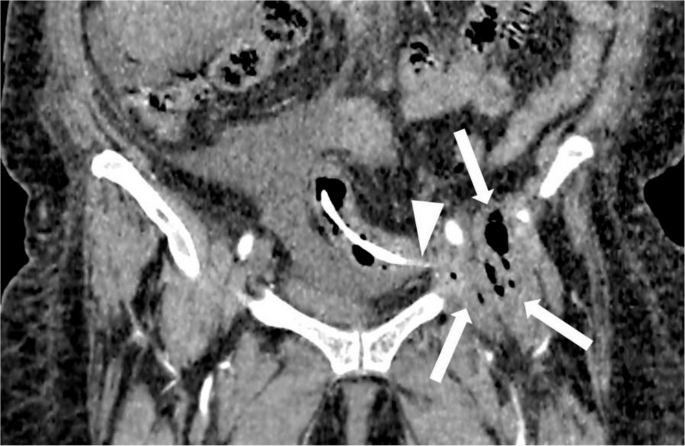

影像学检查显示,一根弯曲的胆道支架从盆腔中部延伸至左下腹,经过髂耻线和髂坐线。即使在单投影X光片上,也能清晰看到支架的远端外侧末端,其末端终止于左髋臼顶部。支架周围局部骨溶解变化表明支架与骨骼有直接接触。X光片未显示髋关节周围有渗出、皮质边界模糊或硬化现象(图1)。增强腹部和盆腔CT显示支架正确放置在胆总管内,而另一根支架则移位至乙状结肠。移位的支架部分位于结肠腔内,其余部分穿透了结肠壁,穿过脂肪层、左髂腰肌筋膜和髂肌,越过髂骨的弓状线,导致髋臼前部出现局部骨质侵蚀,边缘清晰,轮廓平滑(图2)。在支架附近的小范围内观察到单层线性骨膜反应(图2)。在更外围的区域,髂骨上观察到向髋臼前部延伸的硬化改变,以及皮质不规则和小的硬化边缘的侵蚀灶(图3)。

在移位支架的位置,发现髂腰肌内有一个38 × 25 mm的多房脓肿,壁厚,含有多个气体灶,并显示周围对比增强。脓肿紧邻髂骨皮质,皮质基本完整,未见皮质破坏,向下延伸至髂腰肌囊(图3b和4)。乙状结肠的穿孔壁和盆腔的侧壁在左外髂动脉和静脉后方粘连。移位的支架在这两个结构之间形成了一个薄薄的瘘管,穿孔为自限性。由于她患有充血性心力衰竭,因此出现了肝周、脾周和盆腔积液,这些积液是她全身疼痛的主要原因。多学科团队(包括传染病科、骨科和普通外科)认为,鉴于患者没有急性腹膜炎、穿孔为自限性以及存在合并症,无需进行手术干预。针对脓肿问题咨询了介入放射科专家,但由于病灶位置和患者合并症的情况,未进行脓肿引流。对于左髋部和左腿疼痛,采取了观察性治疗策略,首先治疗腹部病变,观察炎症控制后的疼痛是否缓解。采用保守治疗,包括经验性抗生素(阿莫西林克拉维酸钾3 × 1 g,每日口服3次,环丙沙星2 × 500 mg,每日口服2次,持续6周)和止痛治疗(必要时口服萘普生钠)。最终决定通过直肠乙状结肠镜取出支架,该手术也证实了我们的诊断。

图4

这是盆腔的冠状增强CT图像(软组织窗显示)。可见一根胆道支架穿透了乙状结肠壁(箭头所示)。在移位支架的位置,髂腰肌内有一个38 × 25 mm的脓肿,壁厚,含有多个气体灶,并显示周围对比增强(箭头所示)。脓肿向下延伸至髂腰肌囊